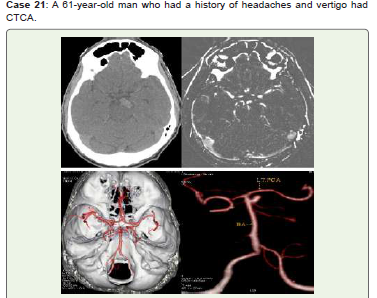

Figure 21:CT Axial non-contrast (A) reveals linear hyperdensity anterior

to midbrain on left side, MIP (B), Virtual dissection of skull (C) and 3D -VR

(D) images reveal distal basilar artery saccular aneurysm with high ellipticity

index projecting to the left side. He was advised endovascular treatment & on

interval follow up.